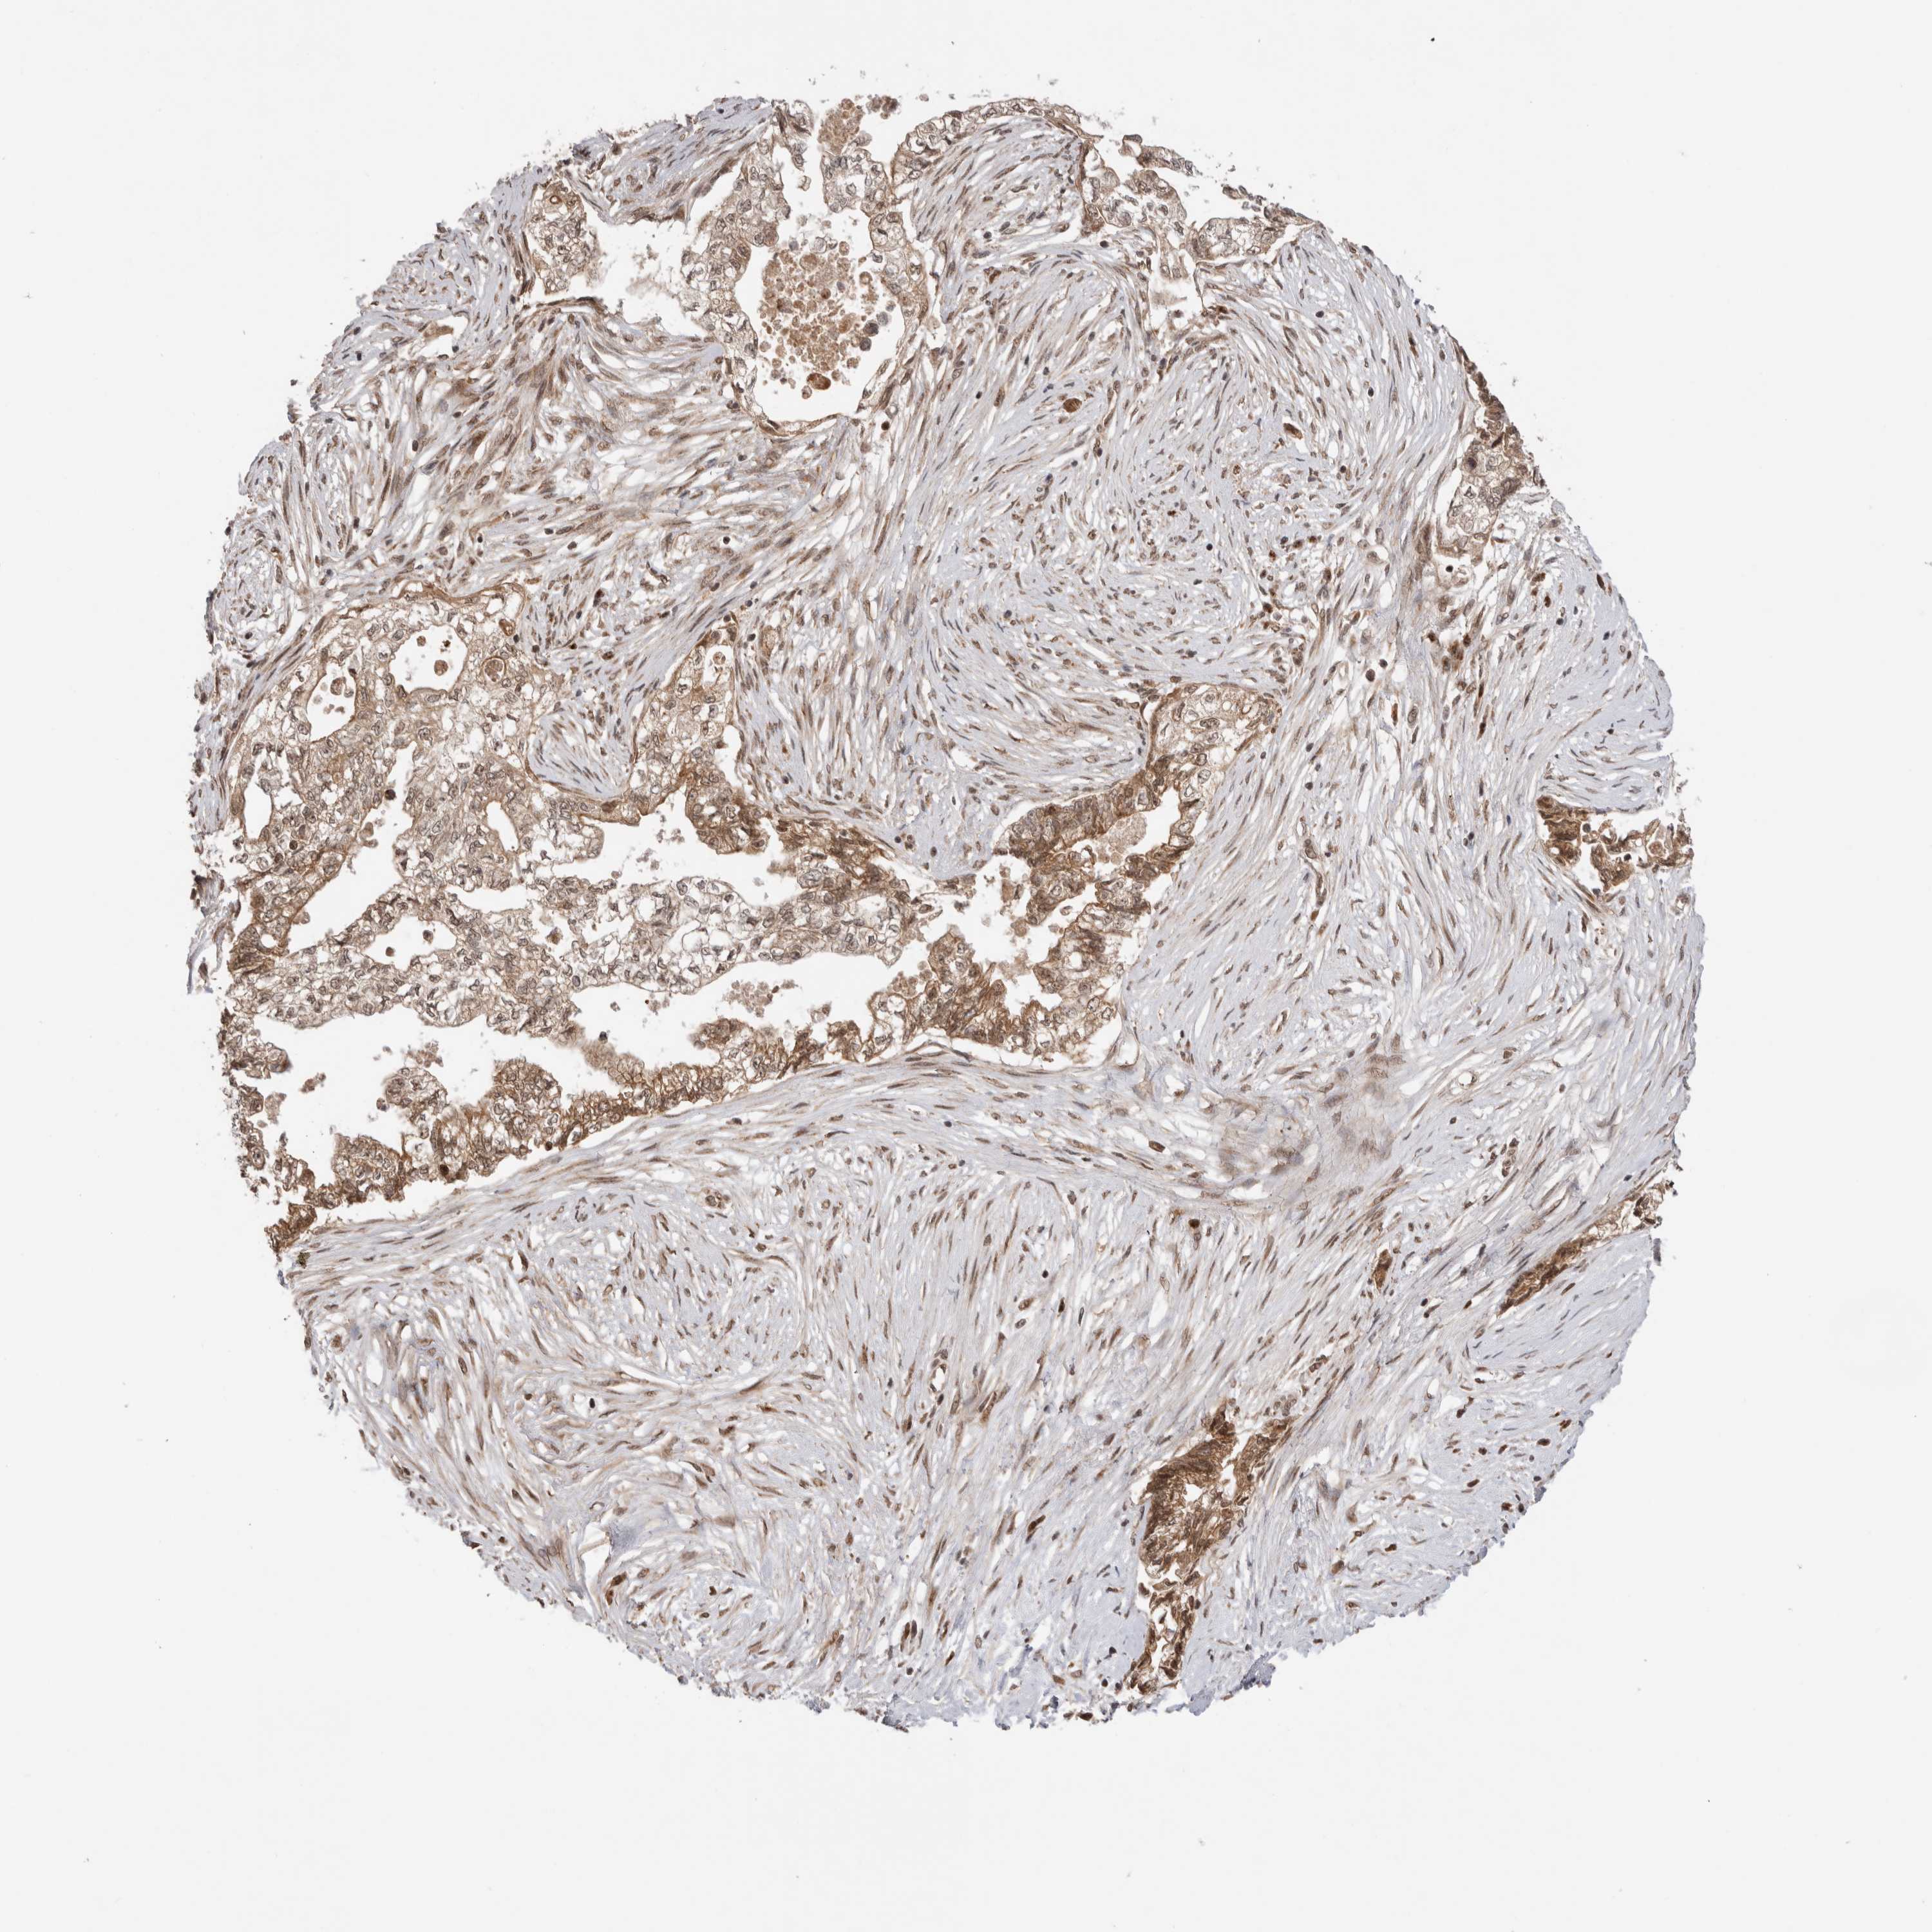

PANCREATIC CANCER - Protein expressioni

A mouse-over function shows sample information and annotation data. Click on an image to view it in a full screen mode. Samples can be filtered based on level of antibody staining by selecting one or several of the following categories: high, medium, low and not detected. The assay and annotation is described here.

Note that samples used for immunohistochemistry by the Human Protein Atlas do not correspond to samples in the TCGA dataset.

Antibody stainingi

Antibody staining in the annotated cell types in the current human tissue is reported as not detected, low, medium, or high, based on conventional immunohistochemistry profiling in selected tissues. This score is based on the combination of the staining intensity and fraction of stained cells.

Each image is clickable and will lead to virtual microscopy that enables deeper exploration of all samples and also displays staining intensity scores, fraction scores and subcellular localization as well as patient and tissue information for each sample.

Antibody HPA025020

Staining

High

Medium

Low

Not detected

Intensity

Strong

Moderate

Weak

Negative

Quantity

>75%

75%-25%

<25%

None

Location

Nuclear

Cytoplasmic/membranous

Cytoplasmic/membranous,nuclear

Adenocarcinoma, NOS